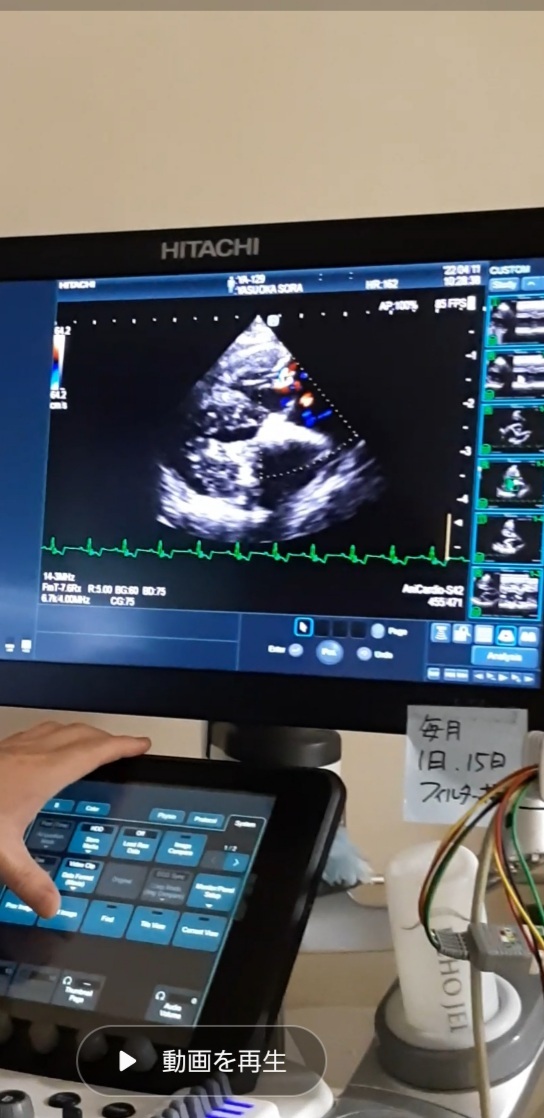

空の心臓の弁はピッタリと合い逆流は見られませんでした。